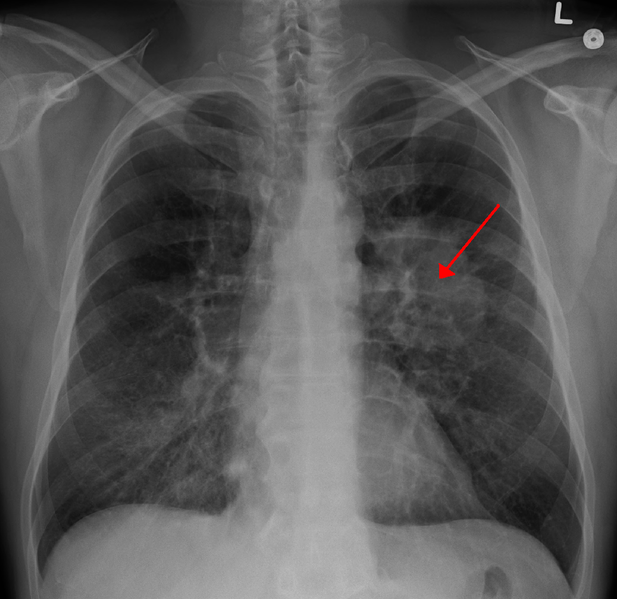

Image info: Xray of Lungs with Cancer : 617 x 599 shared from http://1.bp.blogspot.com/-AWmHN55J-4g/VJ2ZrzFqS6I/AAAAAAAAAnA/frEHQUFqqyg/s1600/LungCACXR.PNG